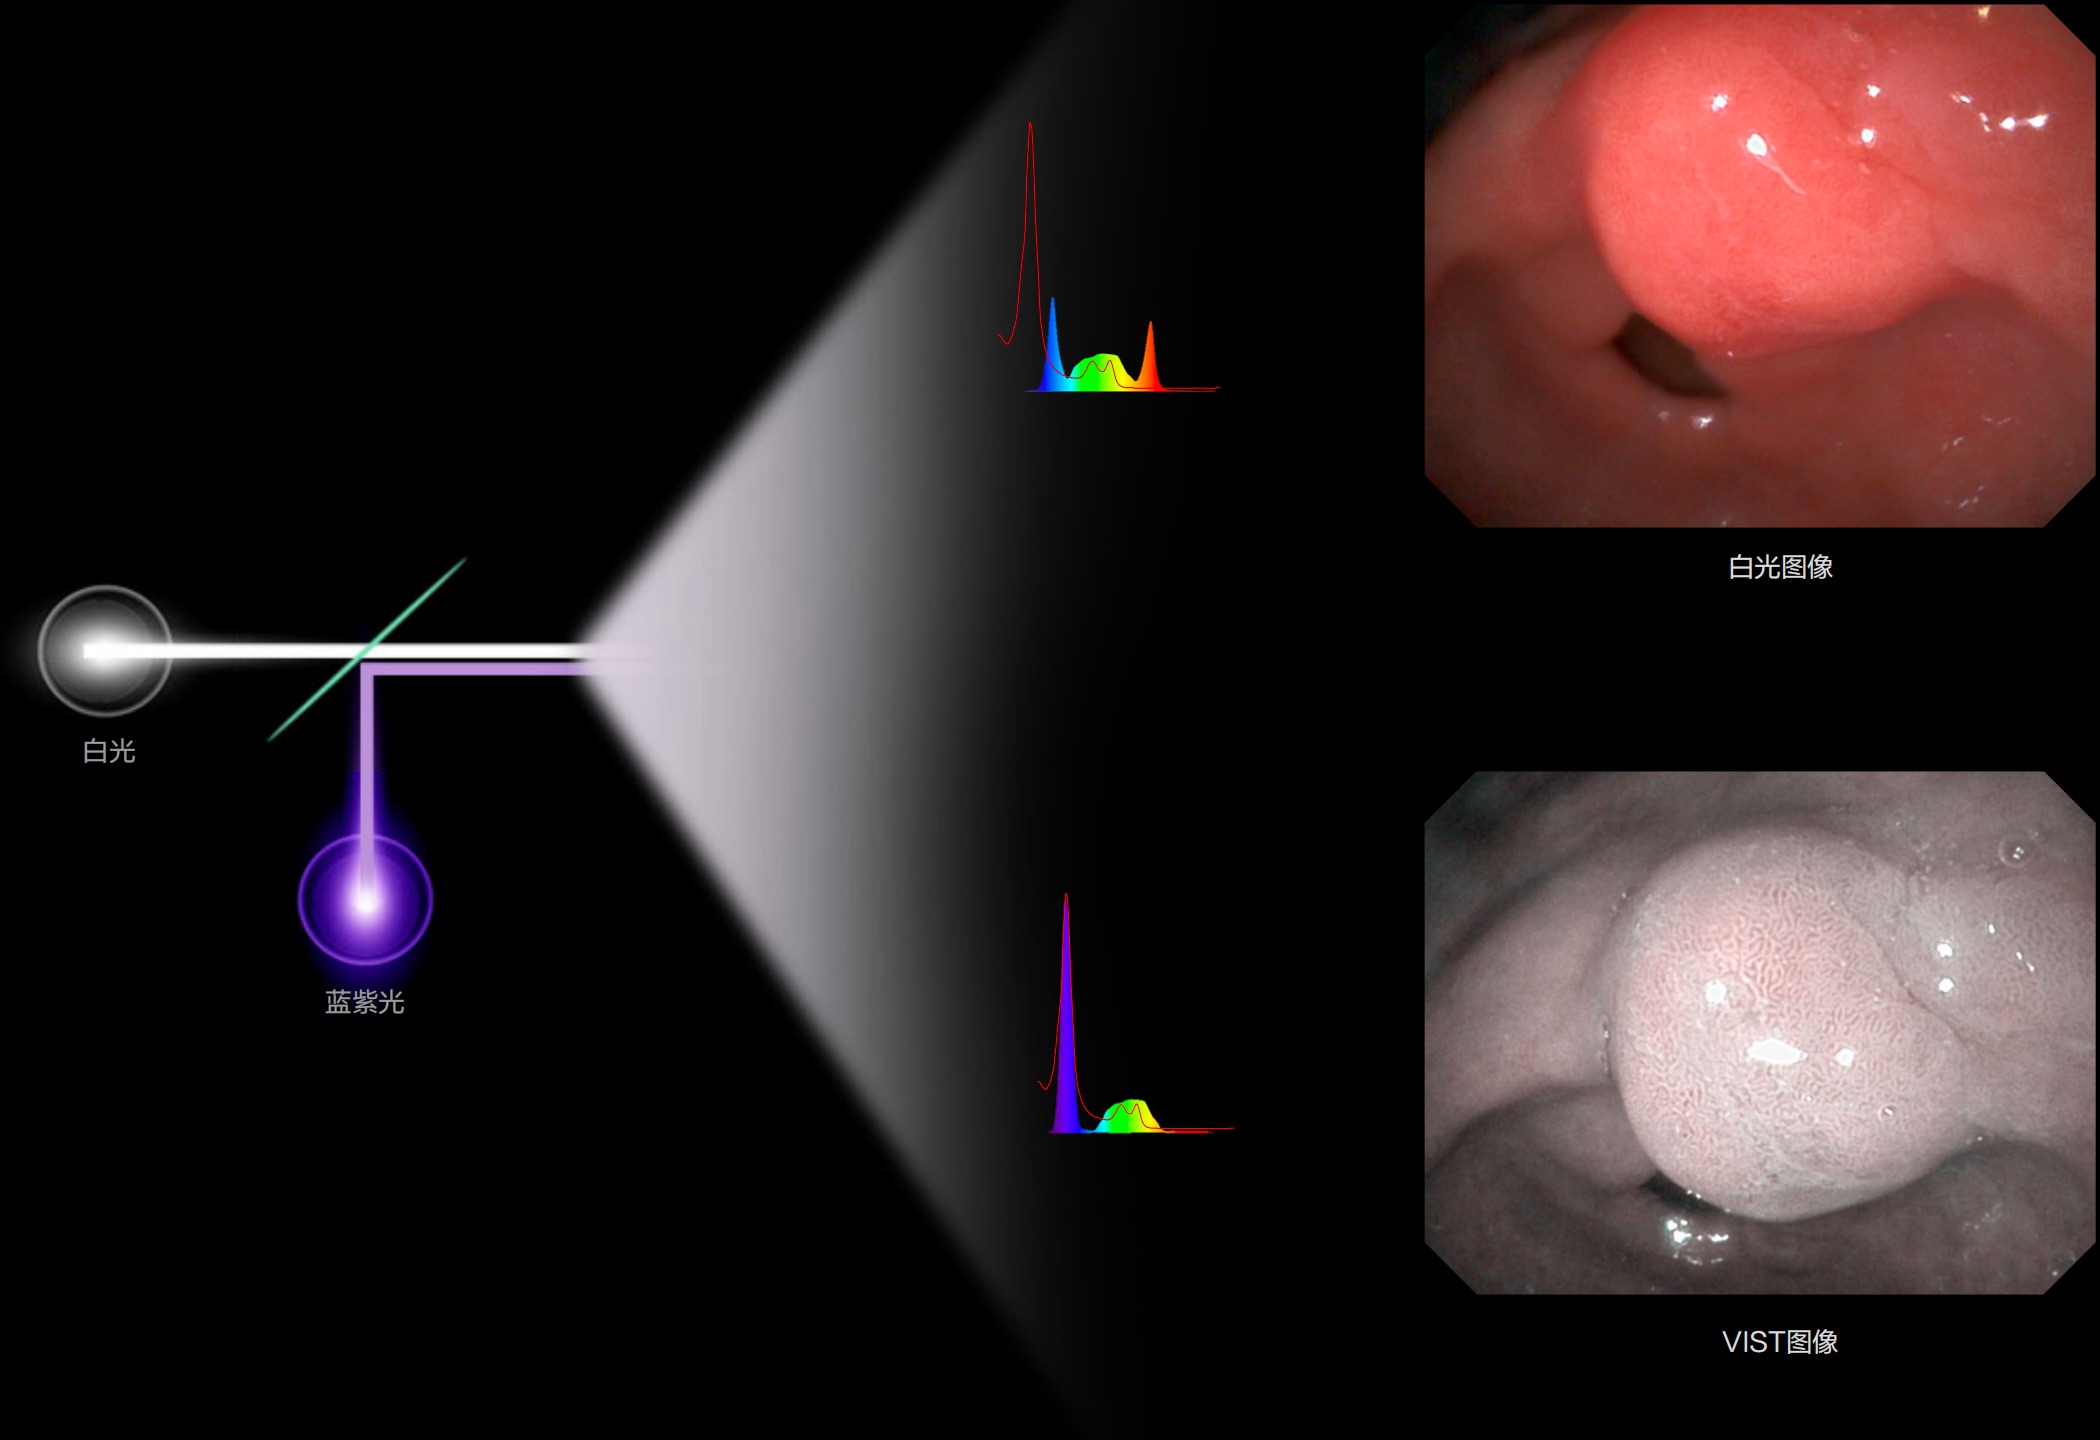

(Versatile Intelligent Staining Technology)

利用了血红蛋白在不同波长吸收下系数不同的原理,设计的一种光学域滤波和数字域滤波结合的染色技术,既保证了图像亮度,又可增强黏膜血管的对比度,充分凸显早期病变的细微结构变化,为临床疾病的观察诊断提供更丰富的参考信息。